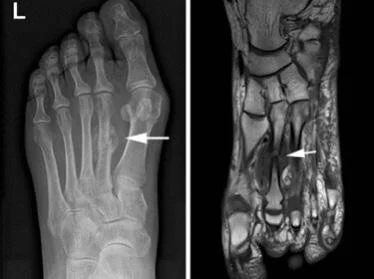

Während Ermüdungsfrakturen durch repetetiven Stress, also biomechanische Ursachen, eher kleine, nicht hauptlasttragende Knochen, wie im Mittelfuß oder das Wadenbein betreffen, kommt es im osteoporotisch geschädigten Knochen auch zu Brüchen der größeren Skelettknochen (siehe oben). Abhängig ist die Lokalisation der Fraktur aber auch von der individuellen Gewichtsverteilung auf die einzelnen Strukturen. Hinzukommen individuelle biomechanische Abläufe beim Laufen.

📸 © springer medizin

Im Prinzip ist eine Stress-/Ermüdungs-/Marschfraktur eine Reaktion des Knochens auf repetitive Belastung (Marschieren, Ausdauerlauf, etc). Die Dauerbelastung führt zur „Ermüdung“ der Knochenstruktur als Stressreaktion. Der Bruch ist letztlich der völlige Einbruch des Knochengerüsts. Ein Ermüdungsbruch äußert sich meist erstmalig durch belastungsabhängige Schmerzen im betroffenen Knochen, der sich mit der Zeit auch zum Ruheschmerz entwickeln kann. Aufgrund der oft schleichenden Symptomatik wird manchmal noch für einen gewissen Zeitraum weitertrainiert. Meist wird auch eher ein muskuläres Problem vermutet und der gebrochene Knochen daher noch längere Zeit belastet, bis man sich dem Arzt vorstellt.

Epidemiologisch zeigt sich, dass Ermüdungsbrüche ein durchaus großes Problem im Leistungs- und Breitensport darstellt. Mehr als ein Drittel der professionellen Langstreckenläufer*innen machen Erfahrungen mit einer Knochenstressreaktion, wie z.B. einem Ermüdungsbruch. Die 1-Jahres Prävalenz (Kennzahl für die Krankheitshäufigkeit) der Leichtathlet*nnen, die eine Ermüdungsfraktur erleiden liegt bei 21%. Zudem kann auch ein zu rascher Wiedereinstieg nach einer Ermüdungsfraktur sowie gleichzeitig ein repetitiver Bewegungsablauf zu einer wiederkehrenden Stressfraktur führen.